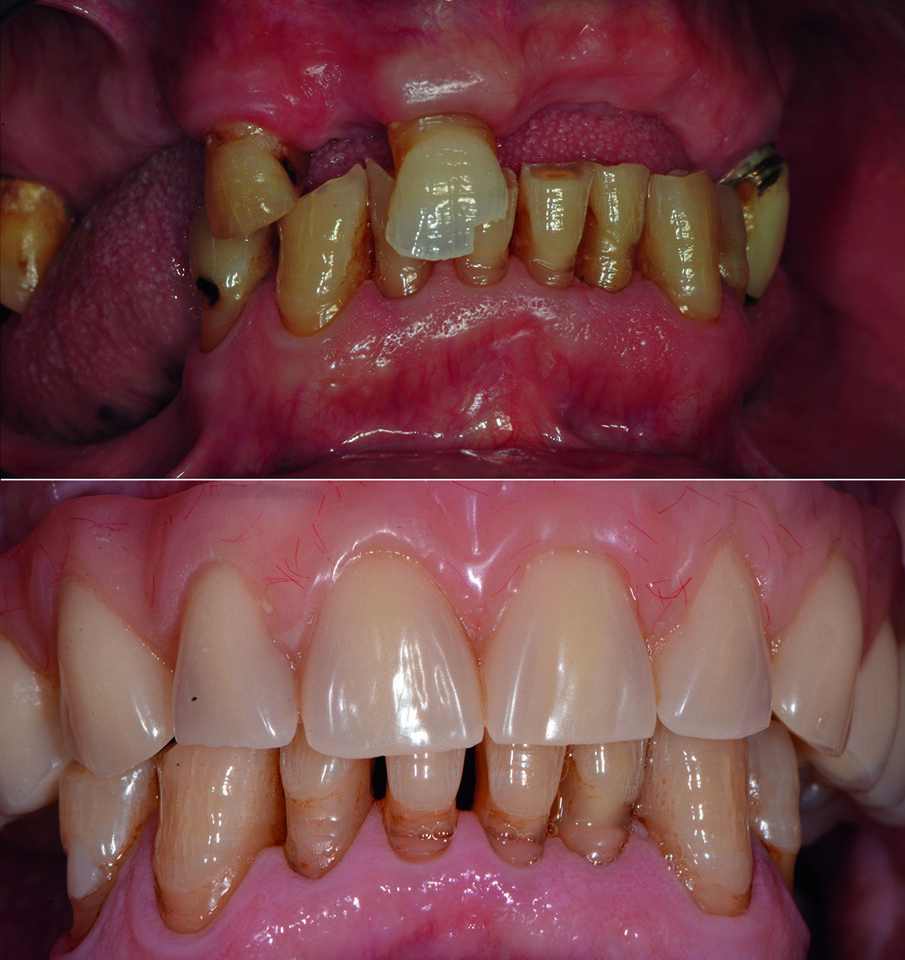

Si presenta alla nostra osservazione un paziente di anni 75, pensionato, con una richiesta di riabilitazione orale. Il paziente presenta edentulia parziale con distruzione dei tavolati occlusali e diminuzione della dimensione verticale (Fig. 1). In sede mandibolare sono conservati gli elementi dentali dal 35 al 45, mentre a livello mascellare residuano 4 elementi dentali con gravi problemi endodontici, di carie e parodontali. All’anamnesi si evidenzia la presenza di un diabete di tipo 2. Nessun problema è stato rilevato a livello ematico e pressorio.

Condividiamo con il paziente la scelta terapeutica di riabilitazione implantoprotesica che nella 1 fase consisterà in riabilitazione occlusale mediante l’applicazione di protesi provvisoria, e successivamente inserimento di 6 impianti nel mascellare a carico ritardato e seguente applicazione di barra per una overdenture. Il paziente necessita di una riabilitazione oro-implantare protesica, in quanto sia all’esame obiettivo che all’esame radiografico presenta una ridotta dimensione verticale che negli anni ha portato alla distruzione degli elementi inferiori dal 34 al 44, e persistenza di 11, 13, 17, 25 che presentano abrasioni e abfrazioni sulla superficie coronale (Fig. 2). Dopo aver condiviso con il paziente le problematiche terapeutiche dovute anche alla sua condizione di patologia sistemica, si decise, di procedere con avulsione dei denti dell’arcata superiore e contestuale inserzione di 6 impianti, per un una riabilitazione implantoprotesica overdenture su barra, a carico ritardato a 6 mesi.

Dopo la terapia chirurgica, si inserisce una protesi totale provvisoria, che il paziente porterà per 6 mesi (Fig. 4b). Dopo i 6 mesi si monta la barra e la protesi totale superiore (Figg. 5, 6), che oltre a migliorare la masticazione e la fonetica del paziente, supporterà anche i tessuti molli, labbro, guancia, ridando al paziente un aspetto del sorriso giovanile e un supporto dei tessuti molli orali delle labbra, delle guance e delle rughe geniene (Figg. 7, 8). Il paziente viene inserito in un piano di mantenimento con un follow-up ogni 3 mesi (Fig. 9).